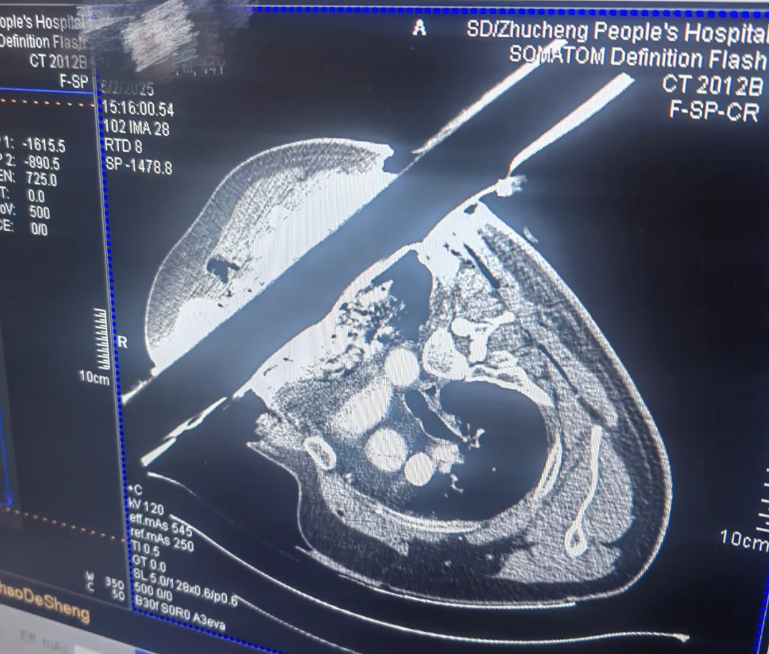

时间拨回到5月2日下午2点,劳动节假期中一个寻常的午后。刘先生在一场惨烈的车祸中,被一根1.2米长的钢管前后贯穿胸腔,命悬一线,急需手术。接到急诊通知的胸心外科主任、主任医师曹瑞实没有丝毫犹豫,马上组织人员术前准备,一场与死神的极限竞速就此开始。

术中探查发现大量胸腔积血,钢管贯穿左肺、紧邻左肺动脉、胸主动脉,距离心脏仅1.5cm!同时,多发肋骨骨折、肩胛骨骨折、左肺裂伤、活动性出血。面对如此严重外伤,曹瑞实带领团队仔细认真修补肺组织、进行肋骨重建防止胸壁塌陷变形。经全力抢救,手术历时3小时顺利结束,患者成功脱离生命危险。